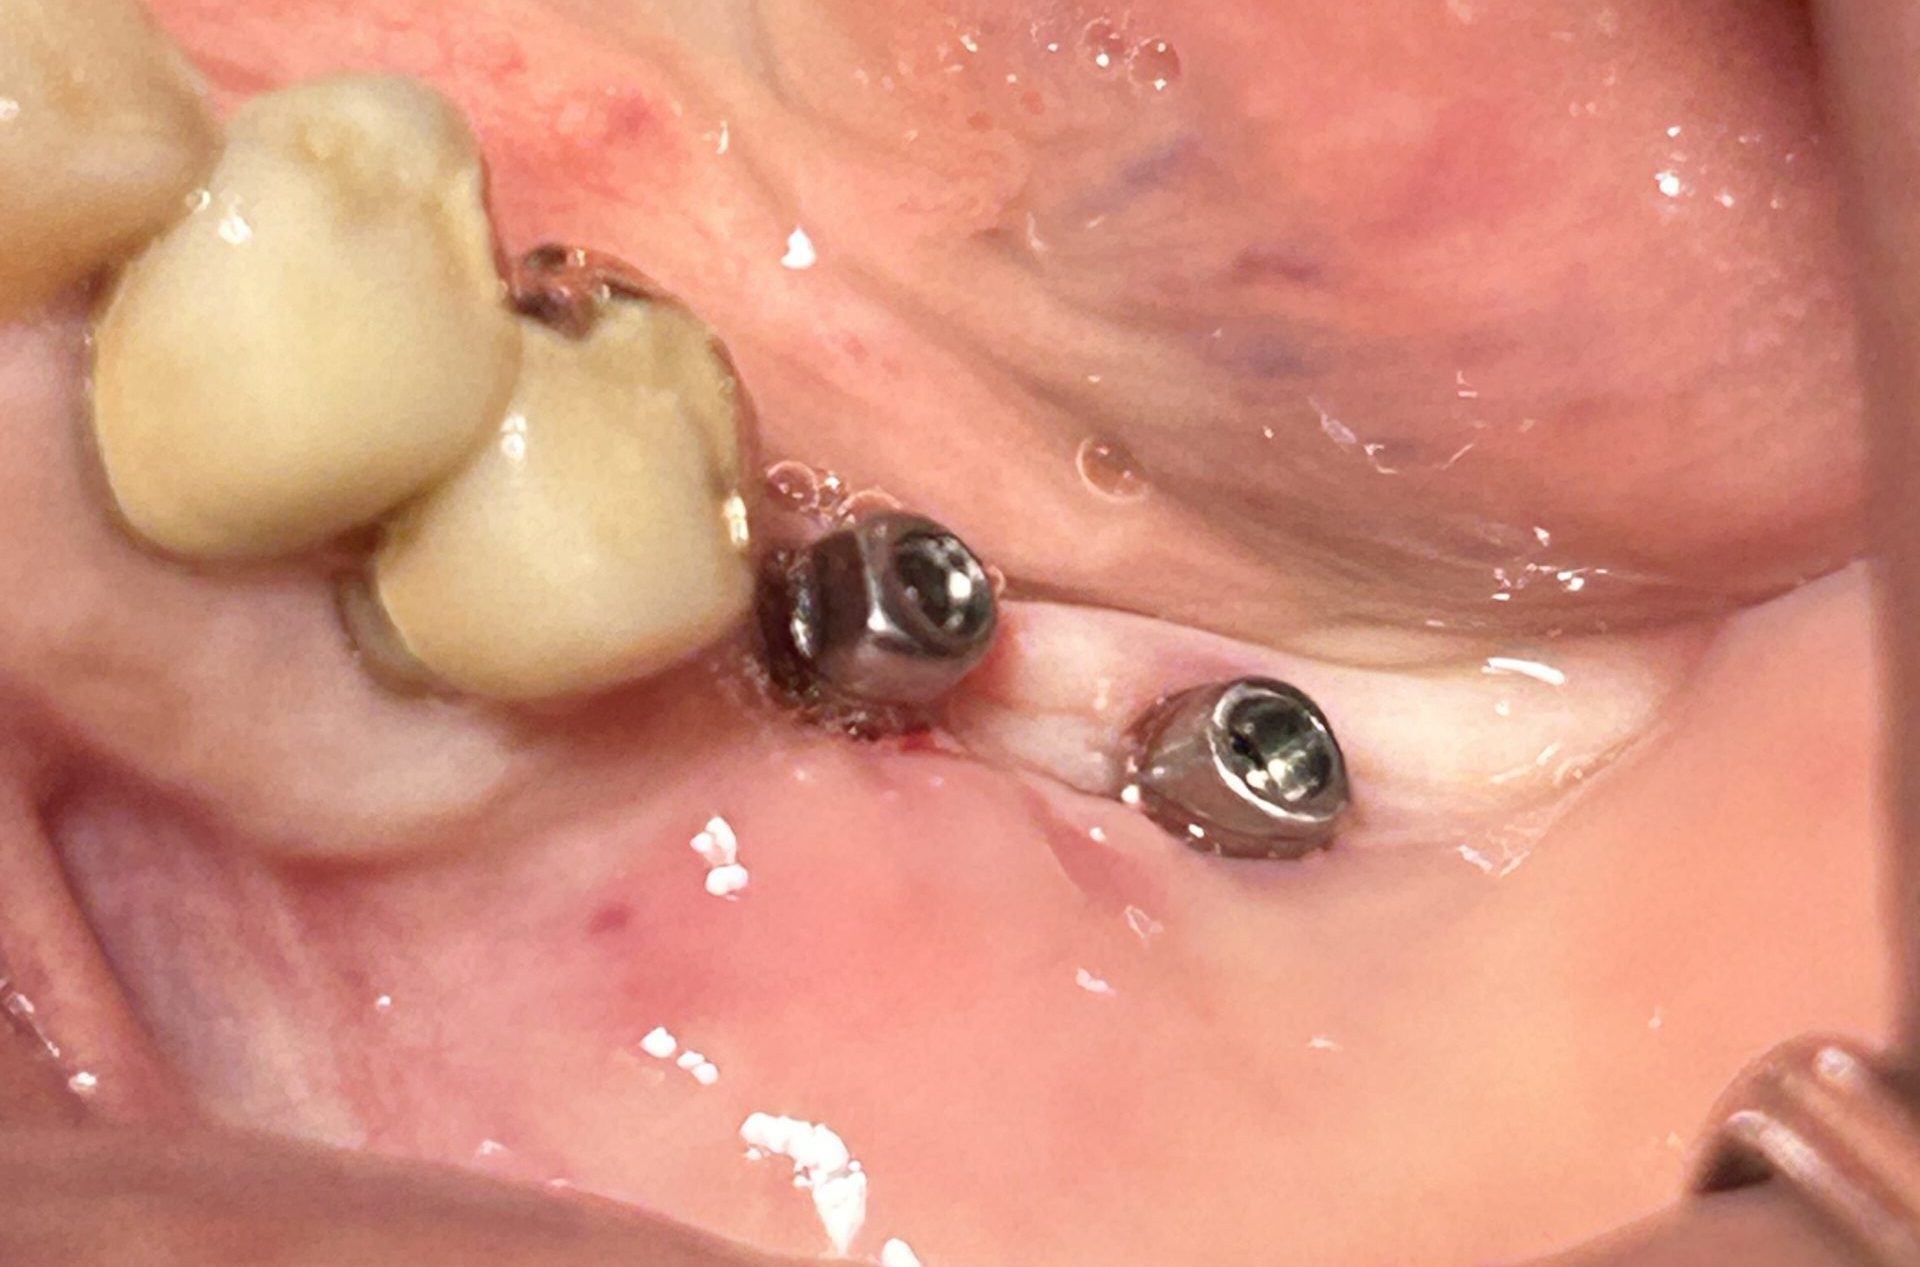

2. 骨としっかり結合する表面構造

インプラントの表面に、独自の微細な加工(サンドブラスト&酸エッチング)を施しています。

-

骨形成を促進: 表面積を広げることで、骨が新しく作られるのを促し、インプラントと骨がより強固に、安定して結合するのを助けます。

3. 「噛む力」を効率よく逃がす独自デザイン

インプラント表面に微細な骨形成を認めていることがわかります。